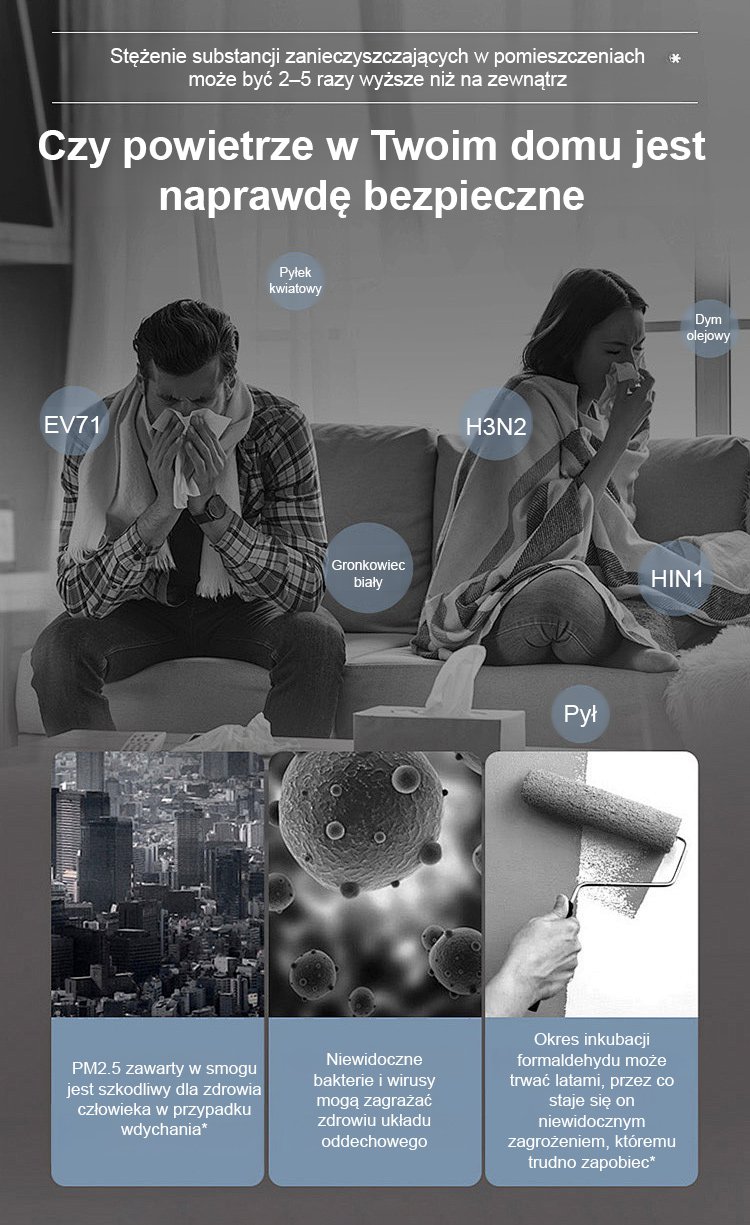

Złoty diament rośliny zielone【Król uzdrawiania płuc】

Złoty diament rośliny zielone【Król uzdrawiania płuc】